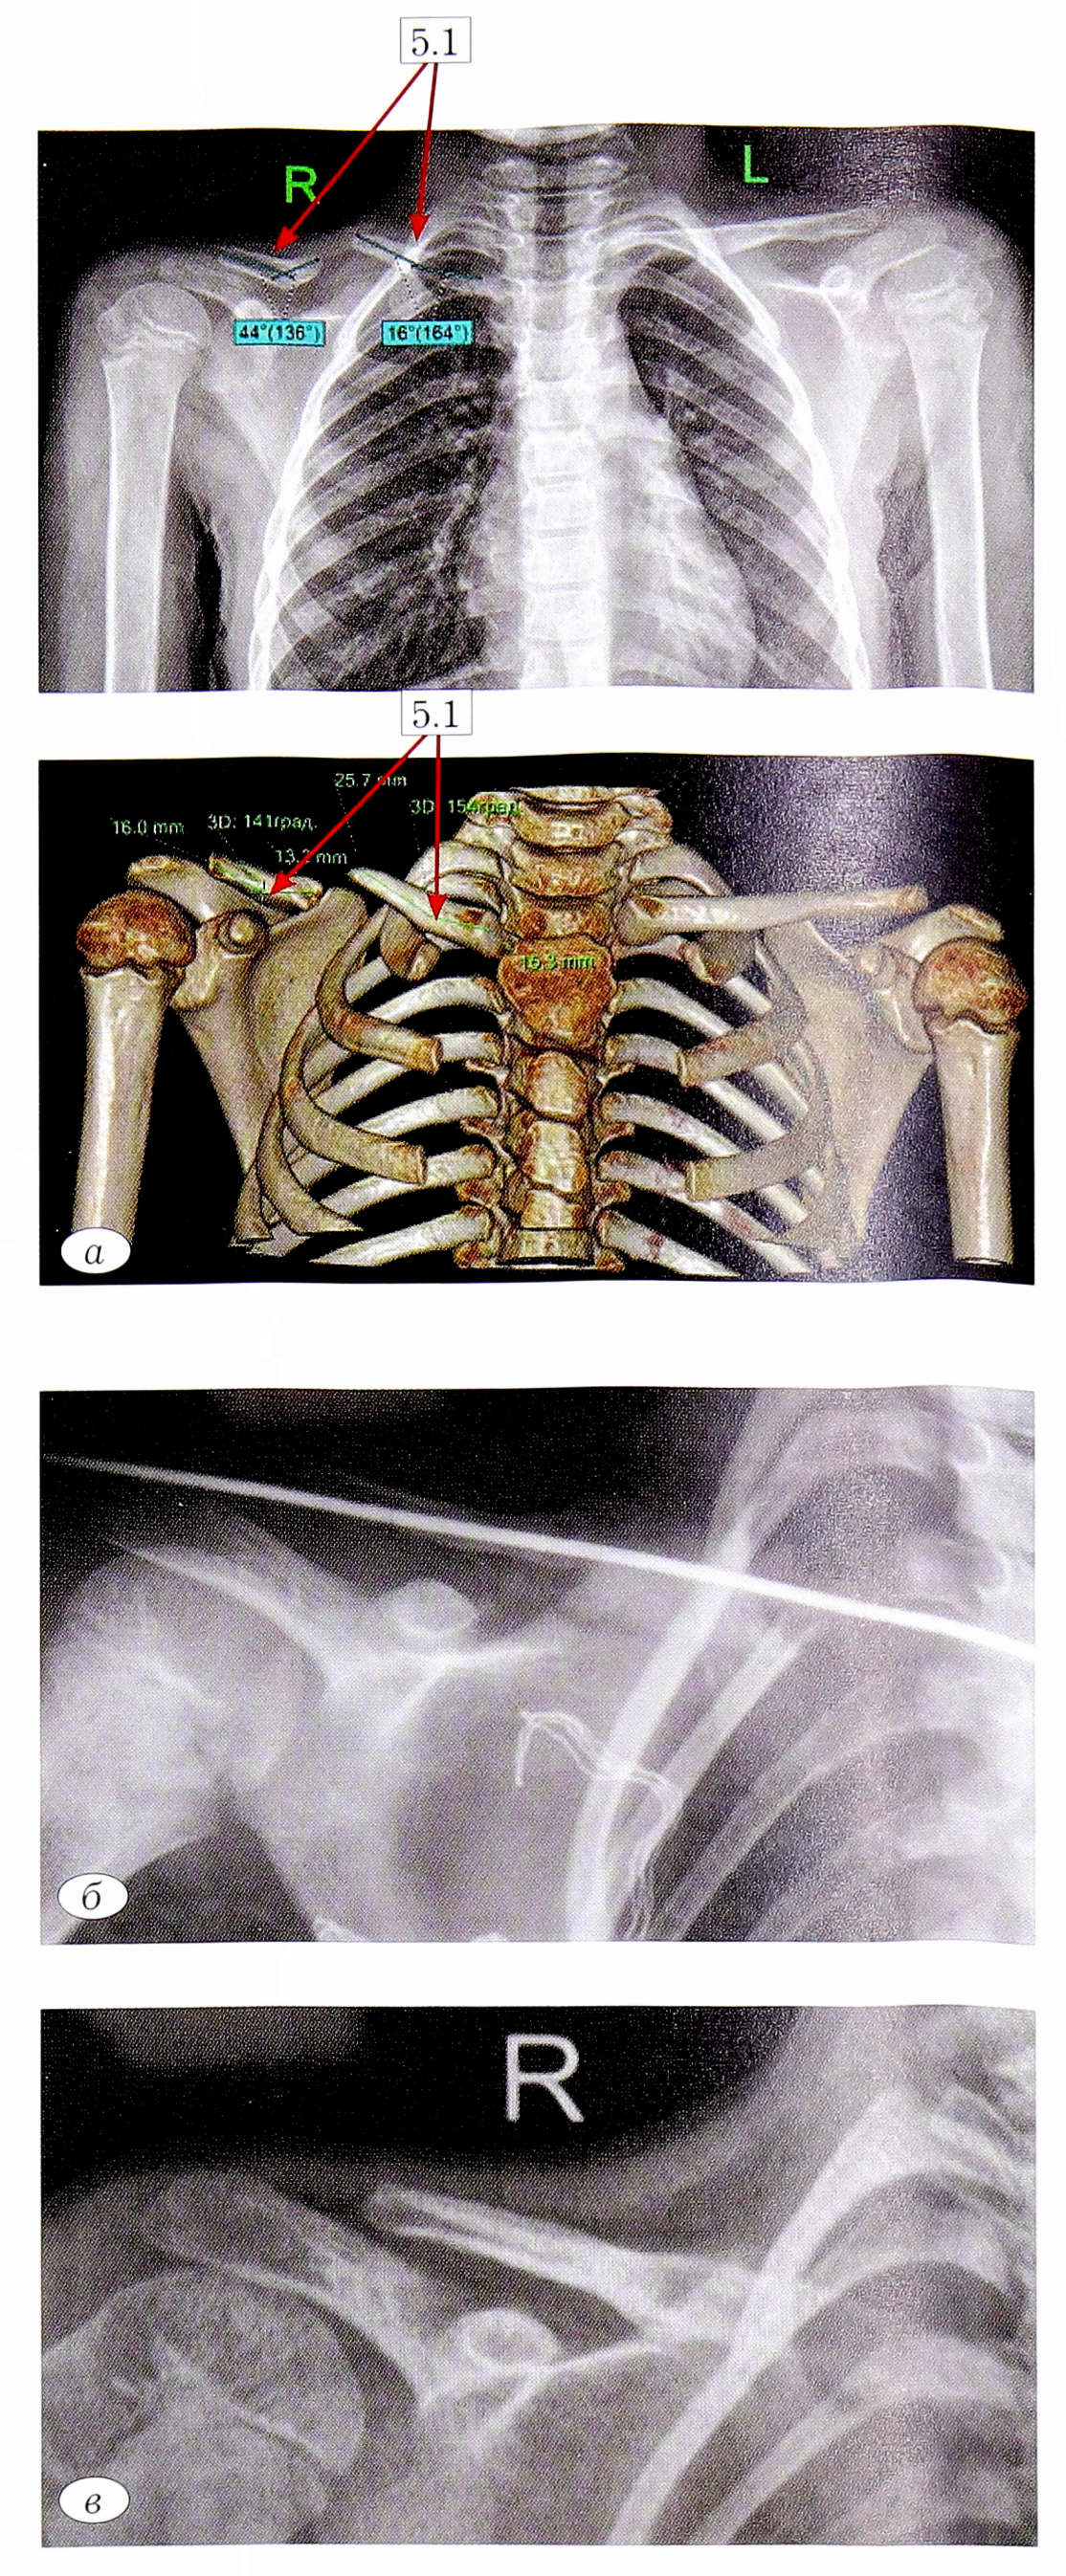

Поскольку основными принципами лечения детей с ВЛСК являются устранение деформации костных фрагментов и восполнение дефицита костной ткани, важную роль в планировании хирургического вмешательства играет КТ-исследование ключицы с 3В-реконструкцией, которое позволяет объективно оценить величину укорочения ключицы, диастаза между концами костных фрагментов, варианты деформации костных фрагментов. При выборе костно-пластического материала было отдано предпочтение свободным костным аутотрансплантатам. Иммобилизацию надплечья осуществляли в среднем в течение 2-3 мес повязкой Смирнова— Вайнштейна. При наличии явных признаков перестройки костных аутотрансплантатов и формирования компактной костной ткани повязку снимали и в течение 2 мес рекомендовали разгрузку и иммобилизацию надплечья мягким плечевым ортезом (рис. 5, а, б, в).

Рис. 5. Пациент И. Клиническое наблюдение. Рентгенограмма и КТ до лечения (5.1 — вершины деформаций фрагментов ключицы); б — рентгенограмма интраоперационно; в — рентгенограмма через 1 год после операции.

Fig. 5. Patient I. Clinical observation. Radiograph and CT scan before treatment (5.1 — vertex deformationfunctions of fragments of the clavicle); b — x-ray intraopration; in the radiograph 1 year after surgery.